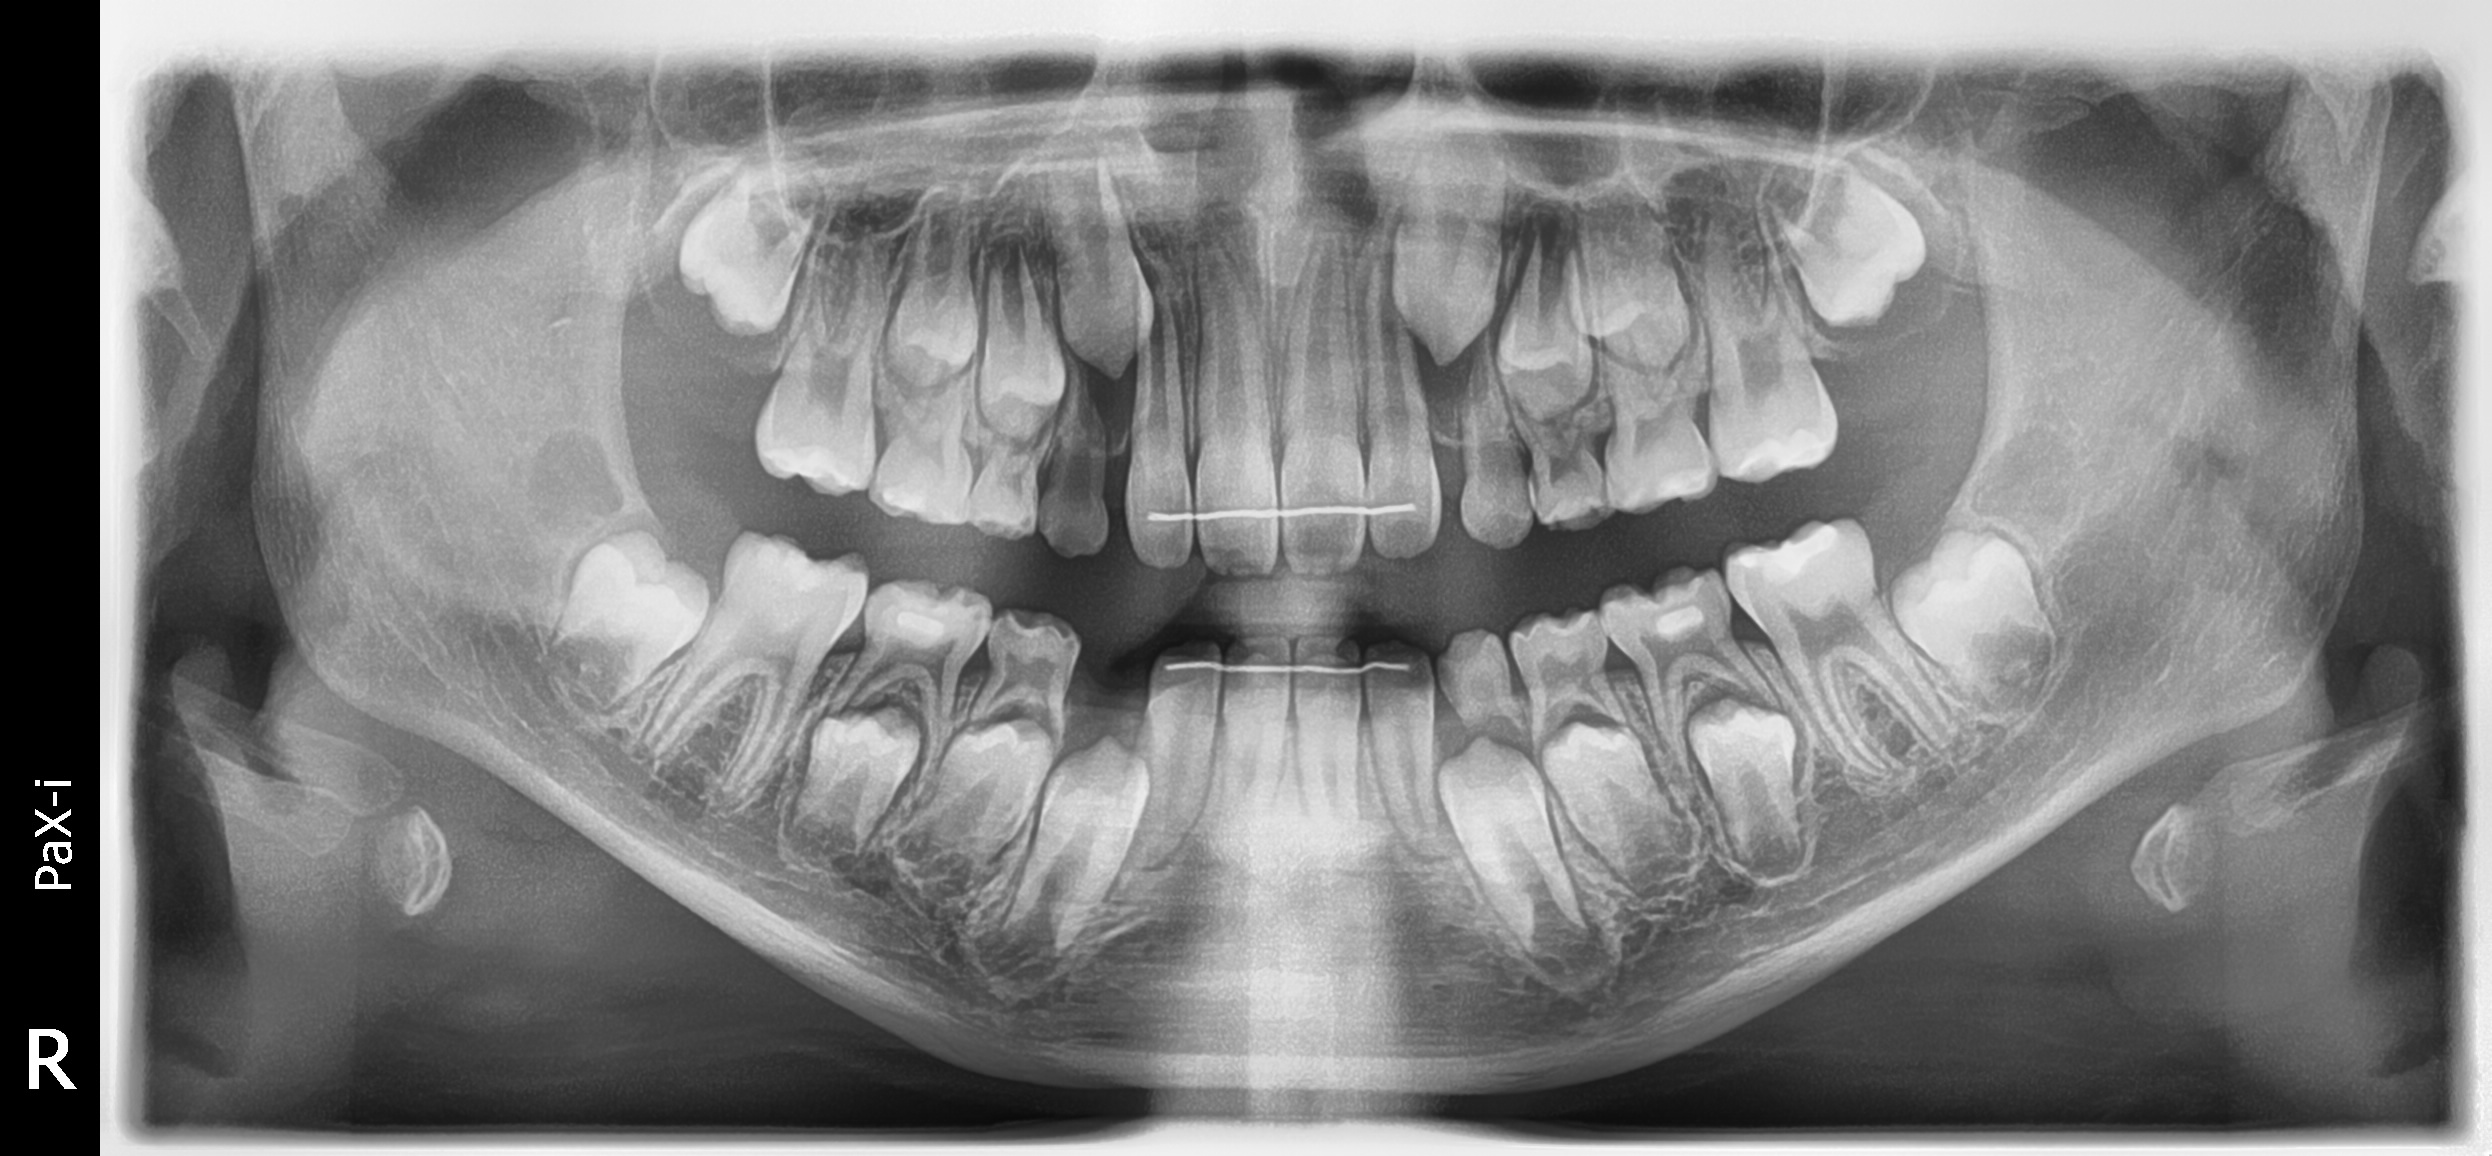

초진 사진입니다. 고르지 못한 앞니와 치아의 회전으로 인한 위아래 앞니의 부딪힘이 발생하고 있습니다. 또한 위아래 앞니의 뻐드러짐과 돌출이 보입니다.

종료 후 x-ray 사진

치아가 나올 공간을 모두 마련해놓았으니 이제 예쁘게 나올 수 있을거에요!